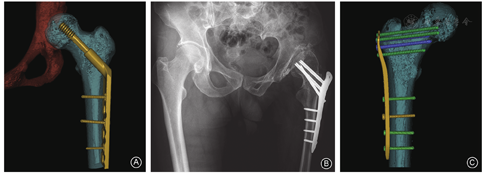

几十年来,国内外临床医生始终坚持着术前设计。基于多排螺旋CT技术的多元化成像技术作为计算机辅助术前计划的核心要素,对股骨转子间骨折损伤细节的观察与评估尤为重要。在传统股骨转子间骨折的术前设计中,骨科医生常根据影像学检查的二维图像,通过大脑的想象还原出骨折三维形态特征,采用手工绘图、自行裁剪或应用数码相机拍摄、打印、再裁剪、比对内固定物等方式,以上诸多方式均依赖于医生丰富的临床经验和主观想象,其准确性和直观性欠佳。计算机辅助术前设计可弥补传统术前设计的不足,构建出结构丰富、带比例尺的高精度股骨近端三维图像,能获得多角度、空间立体感强的图像,可使不具备专业图像处理能力的骨科低年资住院医生快速完成一系列虚拟手术操作,如转子间骨折块的三维分割、模拟复位、内固定物模拟置入等,从而实现精准的术前规划,寻找到最佳的手术入路、复位的解剖标志,预估适宜的内植入物种类和规格,以达到减少手术创伤、缩短手术时间、提高临床疗效的目的。计算机辅助术前设计是现代手术学发展的必须环节[8]。

近年来,随着内固定技术的发展,手术复位内固定已成为股骨转子间骨折的首选治疗方式。股骨转子间骨折常用手术内固定方式包括:髓外固定系统(图5)和髓内固定系统(图6)。通常,以动力髋螺钉(dynamic hip screw,DHS)、股骨近端锁定钢板(proximal femur locking plate,PFP)、倒置微创固定系统(less invasive stabilization system,LISS)钢板等为代表的髓外固定系统适用于简单、稳定型股骨转子间骨折,即31-A1型和31-A2.1型骨折[12,13]。对于复杂、不稳定型的骨折推荐选用以股骨近端防螺旋髓内钉(proximal femoral nail antirotation,PFNA)、股骨近端顺行联合拉力交锁髓内系统(intertrochanteric antegrade nail,InterTAN)为代表的髓内固定系统,其力臂短、扭矩小、生物力学优势更为明显,骨折固定能获得更高的稳定性[14]。随着髓内钉应用越来越广泛,临床医生手术经验不断积累,即便是简单、稳定型的骨折,髓内固定也正逐步成为股骨转子间骨折内固定的主流[15]。

DHS是治疗稳定型股骨转子间骨折的经典内植入物,其组件包括滑动拉力螺钉、滑动钢板及股骨干皮质螺钉(图5A)。滑动拉力螺钉需准确置入到股骨头的中心,确保骨折沿滑动螺钉进行轴向加压,如螺钉偏向股骨头上方则内固定失效的风险较高。骨干部位使用2~3枚皮质骨螺钉,穿双层皮质将滑动钢板固定于骨面。术中透视应测量尖顶距(即正、侧位X线片上滑动螺钉尖端与股骨头顶点之间的距离之和),当尖顶距<25 mm时,可降低螺钉切出失效的风险[16]。外侧壁的完整性也是使用DHS治疗股骨转子间骨折时需考虑的重要因素之一,必须仔细评估。稳定型转子间骨折伴外侧壁破裂者(如AO 31-A2.1型)应谨慎选用DHS固定[17]。

PFP与股骨近端解剖形态的匹配度高,可重建股骨外侧壁的完整性,近端3枚螺钉分别与钢板呈多角度、多平面的方向置入头颈部,具有较好的防旋和抗剪切力,使得转子间骨折获得理想的对位、对线。锁定螺钉与钢板之间通过锁定孔进行固定后,能够有效预防颈干角变小、骨折部位成角畸形。对于股骨髓腔较细、前弓大或股骨先天性畸形,髓内钉置入困难者,亦可选择PFP固定。应用PFP治疗股骨转子间骨折时,由于股骨近端形态学存在个体间的差异,术中可适当调整钢板的位置,以确保股骨近端3枚螺钉能够准确置入到股骨颈内。在临床工作中,对一些特殊类型的股骨转子间骨折,如小儿麻痹症患者的骨折,其骨骼髓腔较为狭窄,选用PFP治疗更适宜(图5B)。

股骨远端的LISS钢板倒置后与股骨近端解剖结构相似,LISS钢板固定时多枚螺钉能够成角置入到股骨头颈内,可获得成角稳定,其近端把持力较好,生物力学稳定性优于DHS[18]。对于反转子间骨折或累及转子下的粉碎性转子间骨折,且伴有严重骨质疏松的老年患者,可采用倒置LISS钢板进行固定[19,20]。应用倒置股骨LISS钢板治疗股骨转子间骨折属于微创操作,骨折闭合复位或有限切开复位后,钢板自股外侧肌与股骨干之间由近端向远端插入;术中透视下确定钢板位置及骨折复位满意后,近端向股骨头颈内置入4~5枚长度合适的锁定螺钉,注意避免螺钉穿透皮质,远端利用导向器置入4~5枚锁定螺钉(图5C)。